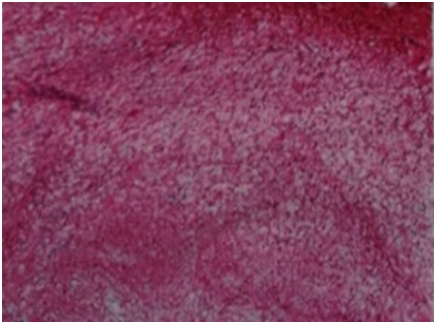

A 53year old lady presented with urgency and frequency for 3months, with two episodes of painless total gross hematuria. She developed acute urinary retention and was catheterized elsewhere and referred to our institute. She had no urological or spine surgeries, no known comorbidities or prior episodes of hematuria. Clinical examination was unremarkable. Ultrasound (US) showed a heterogeneously hypoechoic lesion of 4 x 3 x 4cm in bladder base (Figure 1). Contrast enhanced computed tomogram (CECT) showed a 5 x4 x 4cm well circumscribed hypodense lesion arising from trigone, without hydroureteronephrosis (Figure 2). At cystoscopy, a mucosal bulge measuring around 5 x 5 cm was seen in the right lateral wall extending upto bladder neck and a cecoureterocele was suspected (Figure 3). Transurethral resection (TUR) was done and it showed fragments of tumor tissue composed of spindle cells arranged in sheets and interlacing fascicles, without mitosis or necrosis, suggestive of leiomyoma bladder (Figure 4). Immunohistochemistry showed smooth muscle antigen (SMA) and desmin positivity (Figure 5). Repeat TUR and complete enuceation of the lesion was done. At 6 months of follow up patient is doing well without recurrence or hematuria.

Figure 4 Photomicrograph. Leiomyoma - spindle cells arranged in sheets and interlacing fascicles, without mitosis or necrosis H&E, 40X).